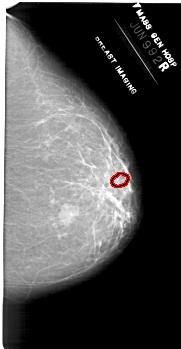

ics_version 1.0 filename A-1953-1 DATE_OF_STUDY 9 6 1992 PATIENT_AGE 50 FILM FILM_TYPE REGULAR DENSITY 2 DATE_DIGITIZED 4 3 1999 DIGITIZER HOWTEK 43.5 SEQUENCE LEFT_CC LINES 6871 PIXELS_PER_LINE 3361 BITS_PER_PIXEL 12 RESOLUTION 43.5 NON_OVERLAY LEFT_MLO LINES 6871 PIXELS_PER_LINE 3526 BITS_PER_PIXEL 12 RESOLUTION 43.5 NON_OVERLAY RIGHT_CC LINES 6616 PIXELS_PER_LINE 3436 BITS_PER_PIXEL 12 RESOLUTION 43.5 OVERLAY RIGHT_MLO LINES 6871 PIXELS_PER_LINE 3631 BITS_PER_PIXEL 12 RESOLUTION 43.5 OVERLAY |

FILE: A_1953_1.RIGHT_CC.OVERLAY TOTAL_ABNORMALITIES 1 ABNORMALITY 1 LESION_TYPE CALCIFICATION TYPE PLEOMORPHIC DISTRIBUTION CLUSTERED ASSESSMENT 4 SUBTLETY 1 PATHOLOGY BENIGN TOTAL_OUTLINES 1 BOUNDARY |